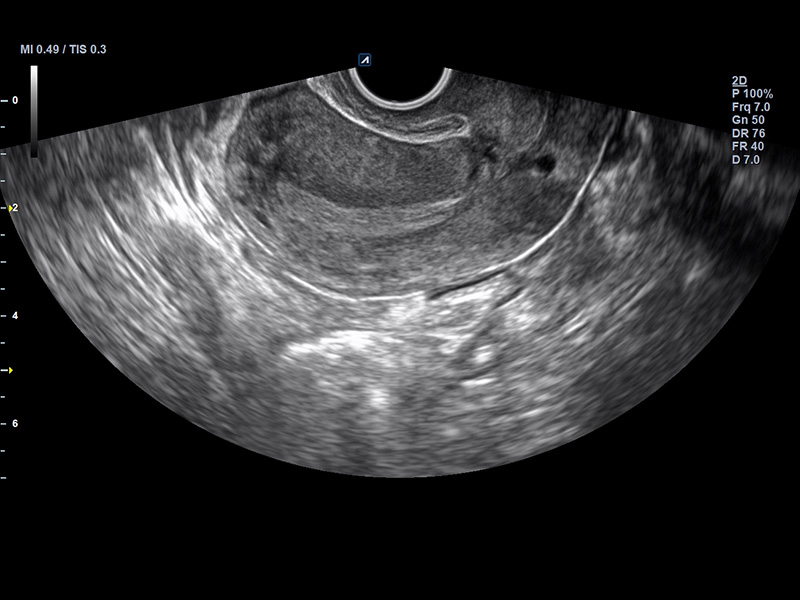

EV2-11H

X+ Crystal Signature endocavity transducer(2~11MHz)

Application:

Gynecology, Obstetrics, Urology, EM

EC2-11H

X+ Crystal Signature endocavity transducer(2~11 MHz)

Application:

Gynecology, Obstetrics, Urology, EM